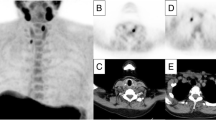

The hallmark of diagnosing PHPT is biochemical testing indicating an inappropriate PTH response with respect to the serum calcium level. Imaging is used to localise the enlarged parathyroids and to determine the optimal surgical approach. In current best practice guidelines, a combination of morphological and molecular imaging is recommended consisting of cervical ultrasonography (US) and parathyroid scintigraphy with 2-phase single-photon emission computed tomography and computed tomography (SPECT/CT) using [99mTc]Tc-methoxy isobutyl isonitrile (MIBI) as radiopharmaceutical [9, 10]. Currently, partial-body [18F]Fluorocholine ([18F]FCH) positron emission tomography and computed tomography (PET/CT) is only recommended after negative or inconclusive MIBI SPECT/CT [11,12,13]. Partial-body [18F]FCH PET/CT, however, might substitute conventional imaging including US and MIBI SPECT/CT [14,15,16], such that imaging can be developed into an [18F]FCH PET/CT-based one-stop-shop localisation strategy [17, 18]. In line with this, a recent network meta-analysis including a total of 8,495 patients from 119 direct competitive studies demonstrated the superior performance of [18F]FCH PET/CT in both patient-based and lesion-based analyses [19].

In this study, current best practice is compared with the [18F]FCH PET/CT-based one-stop-shop imaging strategy. In current best practice, [18F]FCH PET/CT is only provided after negative or inconclusive US and MIBI SPECT/CT (Fig. 1a) [9, 10]. In the one-stop-shop strategy, conventional imaging including US and MIBI SPECT/CT will no longer be provided (Fig. 1b) [17, 18]. As described in the 2021 European Association of Nuclear Medicine practice guidelines for parathyroid imaging, preoperative US provides an additional evaluation of the thyroid that might change patient management, especially in the case of coexisting (suspected) malignant nodules [9]. Therefore, in a separate simulation, we slightly adjusted the one-stop-shop strategy by including preoperative US.

Imaging strategies are visualised. The figure shows (a) current best practice [9, 10] compared to (b) the one-stop-shop strategy [17, 18]. In current best practice, [18F]FCH PET/CT is only provided after negative or inconclusive MIBI SPECT/CT. In the one-stop-shop strategy, conventional imaging including US and MIBI SPECT/CT is no longer provided. Abbreviations: PHPT, primary hyperparathyroidism. US, ultrasonography. MIBI SPECT/CT, single-photon emission computed tomography and computed tomography using [99mTc]Tc-methoxy isobutyl isonitrile. [18F]FCH PET/CT, positron emission tomography and computed tomography using [18F]Fluorocholine